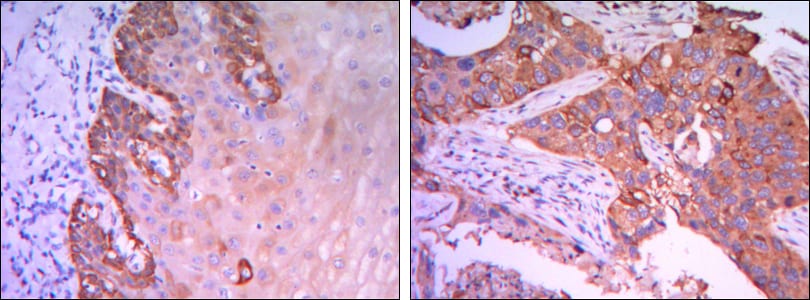

分类: 科研抗体货号: 20430别名: CATX-8; RAB25应用: WB,IHC,IF,FCM反应种属: Human,Mouse